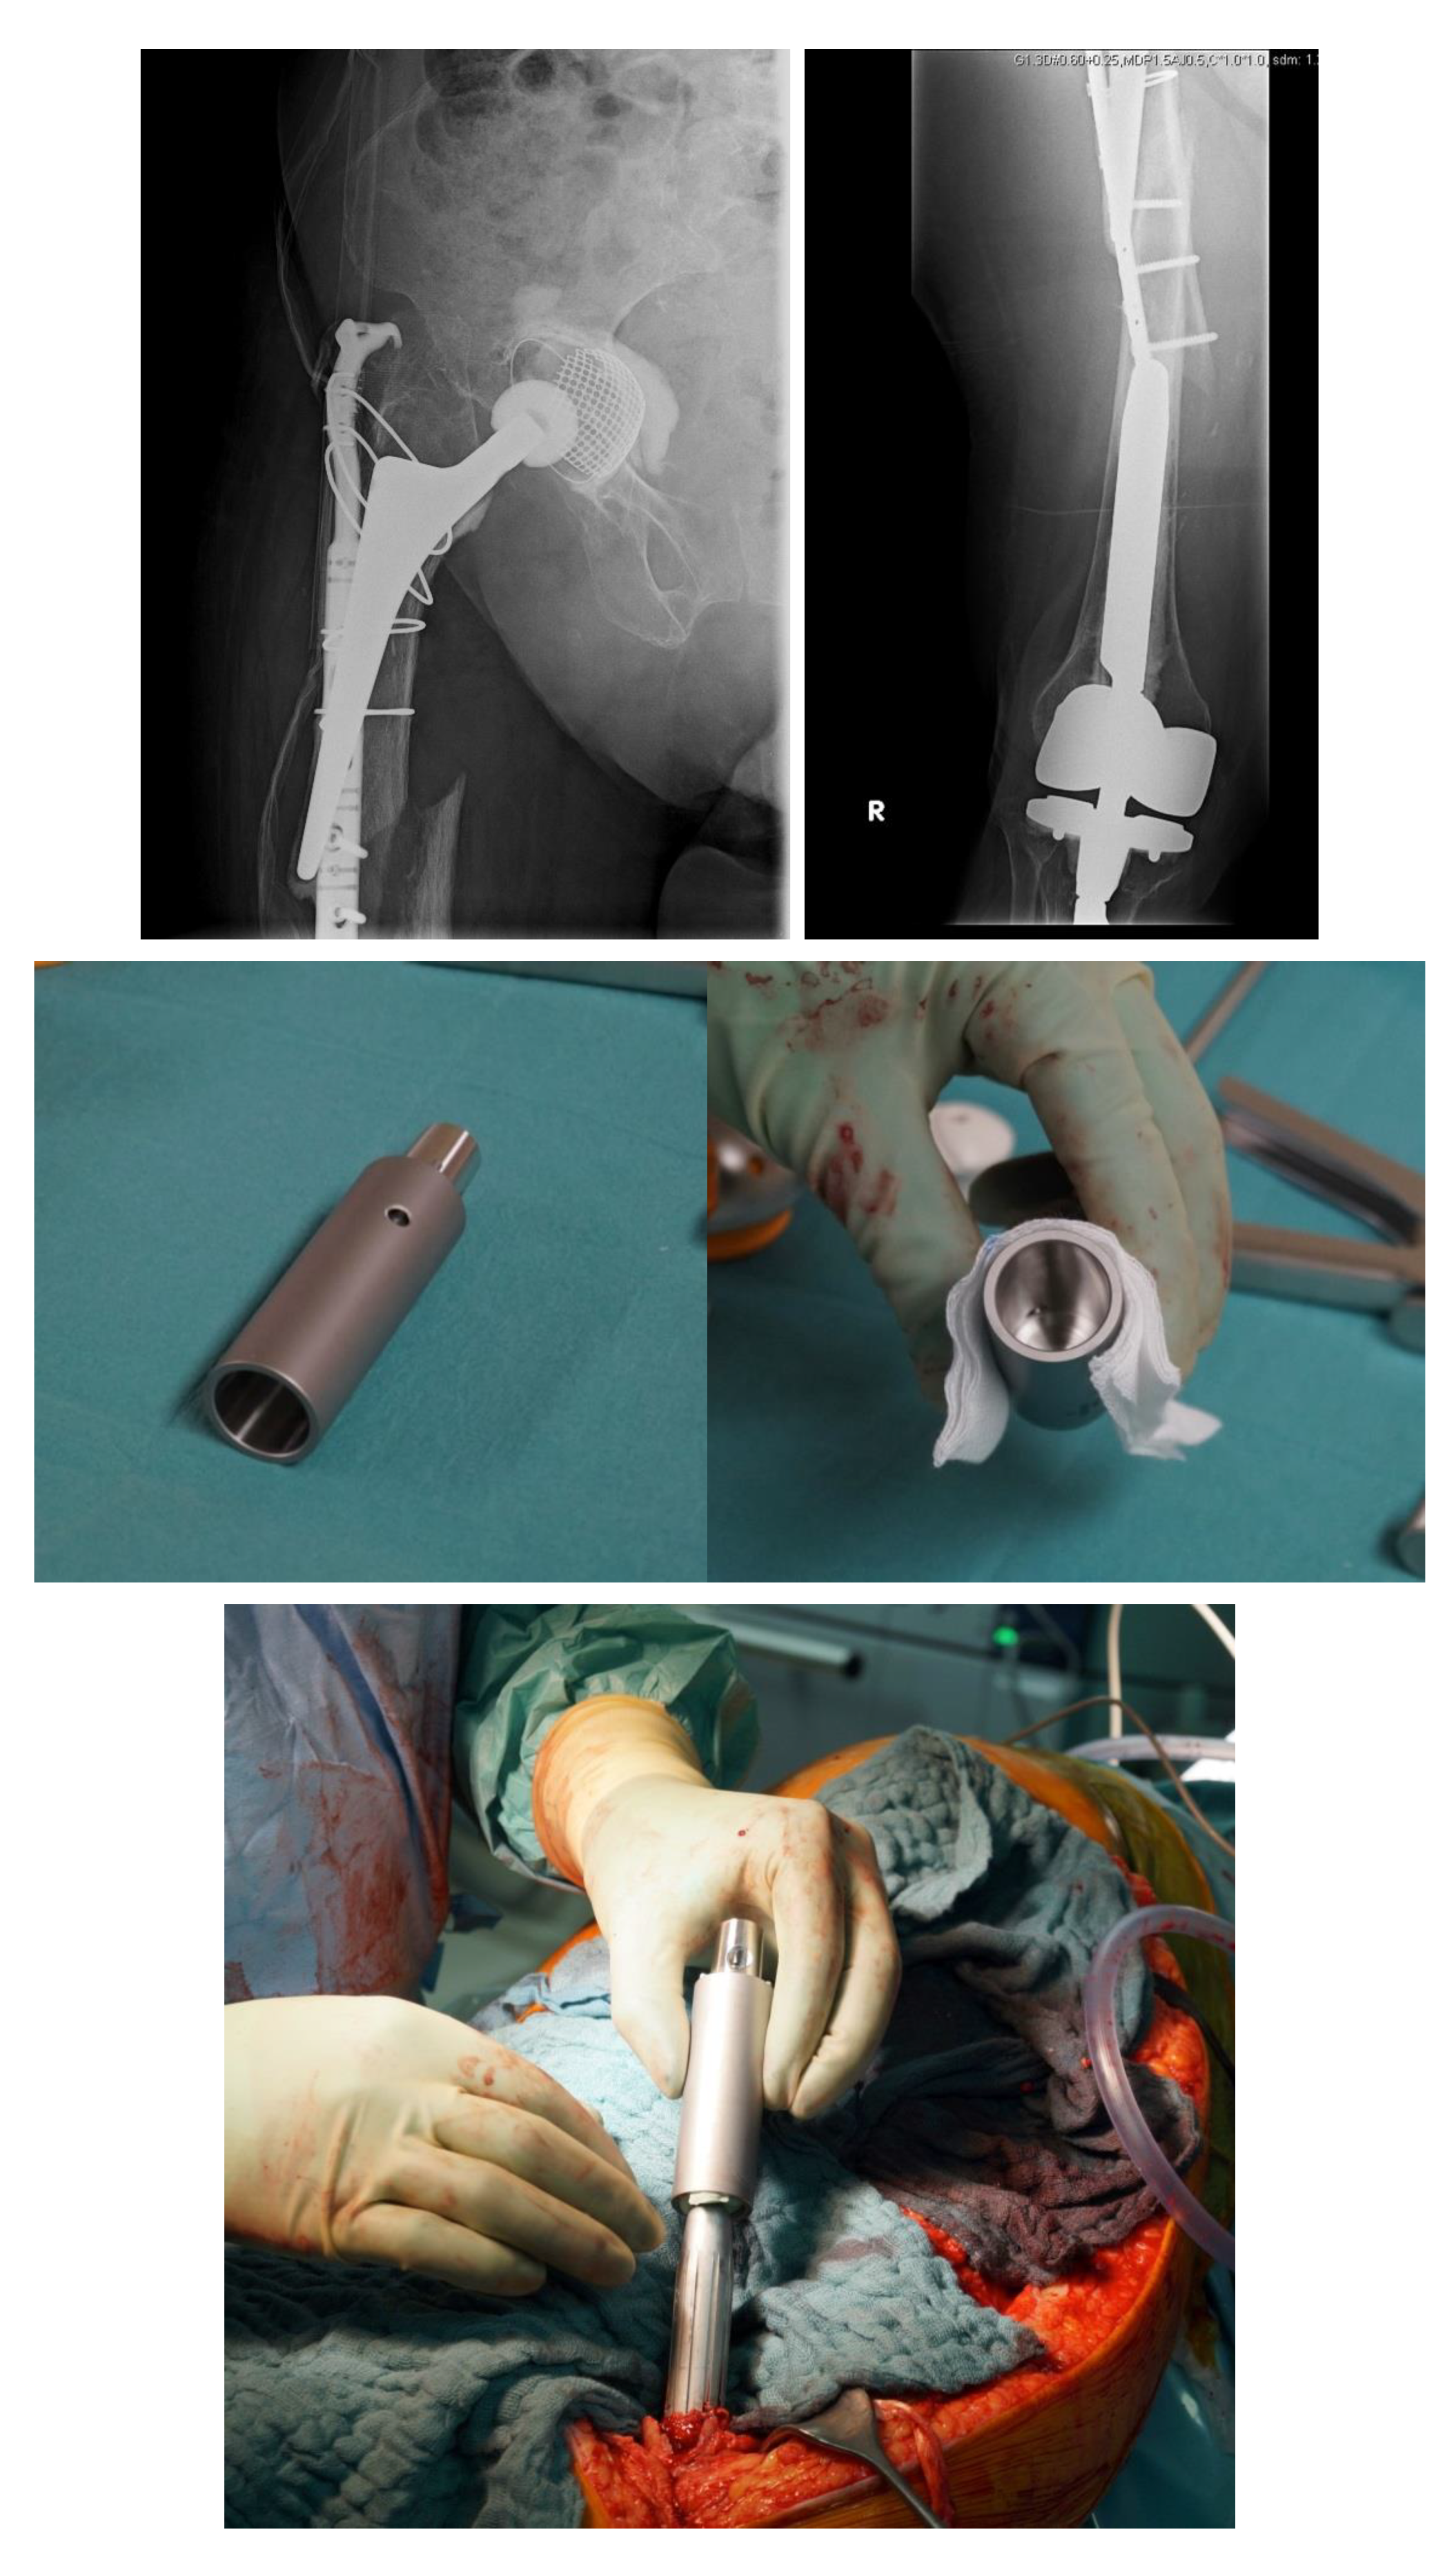

Hence, a special concept improving the bicortical screw fixation around intramedullary devices called the LOQTEQ® VA Periprosthetic Plate or ‘periprosthetic hinge plate’ was established by the company, aap Implantate AG. Multiple insertable hinges create the possibility to place the screws bicortically and alongside the enclosed stem. The square of the two polyaxial locking screws of the hinge constitutes 15 degrees to each direction. Since a central screw can be attached separately, further angle stabilization of the hinges can be achieved. The hinge is not attached to a plate hole, which could be staffed additionally with monocortical screws or cable cerclages in the diaphysis (Figure 3).

Figure 3.

(a) LOQTEQ VA Periprosthetic Plate (with kind permission of aap Implantate AG, Berlin, Germany). (b) Insertable hinge with each of the two variable angle screw options (with kind permission of aap Implantate AG, Berlin, Germany). (c) Periprosthetic fracture around a cemented stable total hip revision arthroplasty. (d) LOQTEQ VA Periprosthetic Plate with mounted aiming device. (e) LOQTEQ VA Periprosthetic Plate with four inserted hinges. (f) Variable angle screw placement around the hip revision stem. (g) Postoperative X-rays. Four hinges with each of the two variable angle screw options were used to fix the plate around the hip stem.

A biomechanical study investigated the characteristics of the LOQTEQ® VA Periprosthetic Plate in comparison with the standard locking compression plate with locking attachment plate, for the treatment of periprosthetic fractures in a Vancouver B1 fracture model.

The LOQTEQ® VA Periprosthetic Plate showed superior biomechanical results (axial stiffness and cycles to failure) compared to the standard locking compression plate in combination with the locking attachment plate [21].